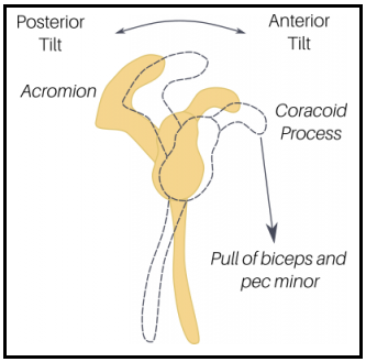

특히 오훼돌기(Coracoid process)에 붙는 소흉근(Pectoralis minor), 이두근건 장두(Short head Of biceps)의 단축은 견갑골을 위에서 아래로, 앞으로 잡아당기게 되면서 견갑골의 앞쪽 기울임(Anterior tilt)을 유발하며 문제를 일으킬 수 있습니다. 따라서 충격파 치료 시 치료포인트가 이두근의 원위부인 팔꿈치 오목 상부인 이유가 됩니다.

소흉근, 이두근 단두의 단축 -> 앞쪽기울임(Anterior tilting) 상태가 유지 -> 충돌 증가